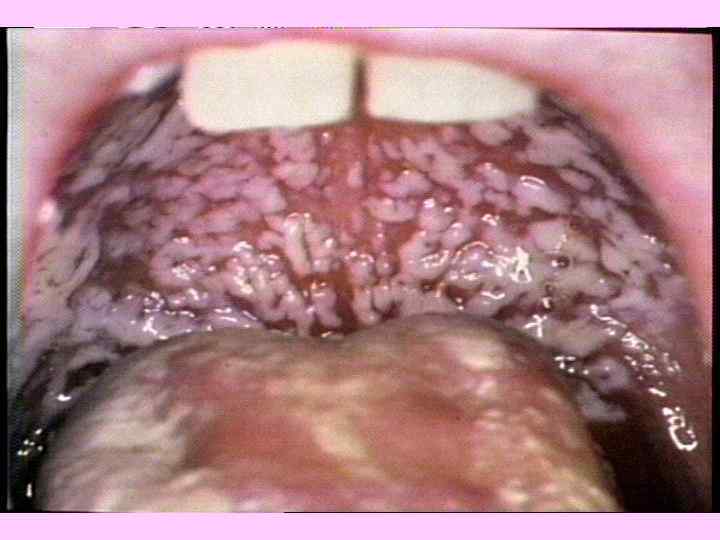

КЛАССИФИКАЦИЯ ГРИБКОВЫХ ЗАБОЛЕВАНИЙ ПОВЕРХНОСТНЫЕ МИКОЗЫ ТРИХОФИТИЯ МИКРОСПОРИЯ ЭПИДЕРМОФИТИЯ КАНДИДАМИКОЗ Дерматофитозы (около 40 видов возбудителей) ГЛУБОКИЕ И СИСТЕМНЫЕ МИКОЗЫ КАНДИДАМИКОЗ ГИСТОПЛАЗМОЗ КРИПТОКОККОЗ КОКЦИДОИДОЗ АСПЕРГИЛЛЕЗ БЛАСТОМИКОЗ